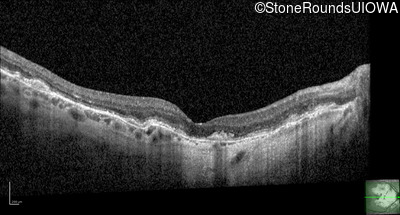

Optical Coherence Tomography - Left - 20/20 -2

Exemplar / OCT Stack